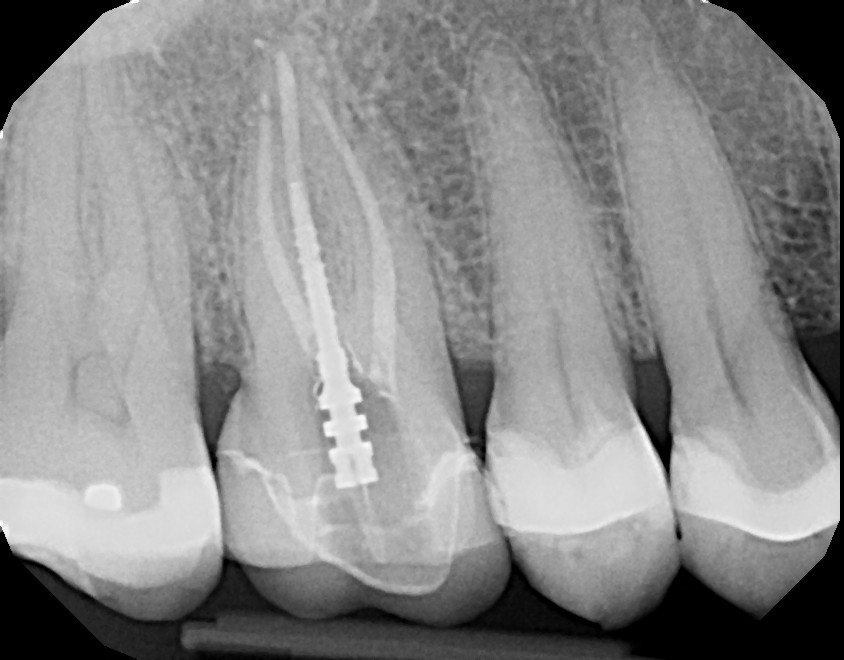

This is a first maxillary molar (tooth #3) that over time required a crown due to a large failing filling. On average, fillings last 5-8 years depending on the size and type of filling with proper oral hygiene, including daily flossing. This patient was advised of possible sensitivity that can occur after crown preparation. Prior to final/permanent crown cementation, tooth #3 became extremely sensitive to hot, cold, and bite and required root canal therapy. With patient education and referral to an endodontist, the final crown was not cemented on prior to root canal therapy. This avoided additional, unnecessary steps. Always ask your dentist/endodontist questions if you feel something doesn't feel right with your teeth, especially after dental work.